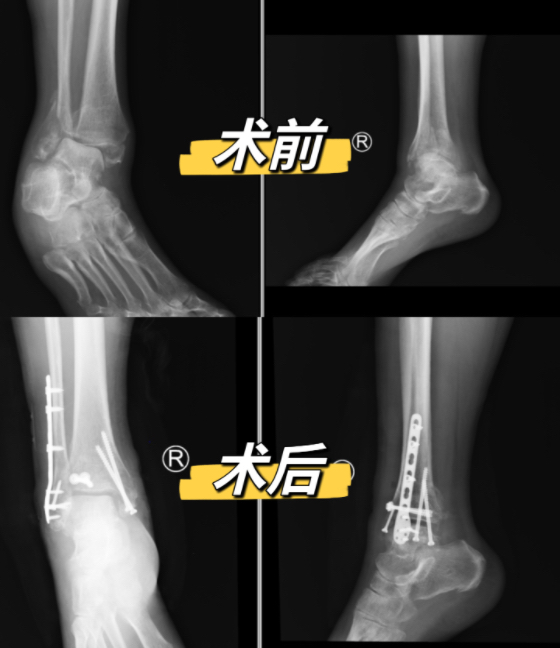

近日,湘雅常德医院骨科为一例右踝肿胀畸形患者顺利实施陈旧性踝关节骨折修复术。术后,患者踝关节畸形得到了矫正,经过一段时间调养后,便可下地活动。 患者术前、术后对比图 右踝肿...